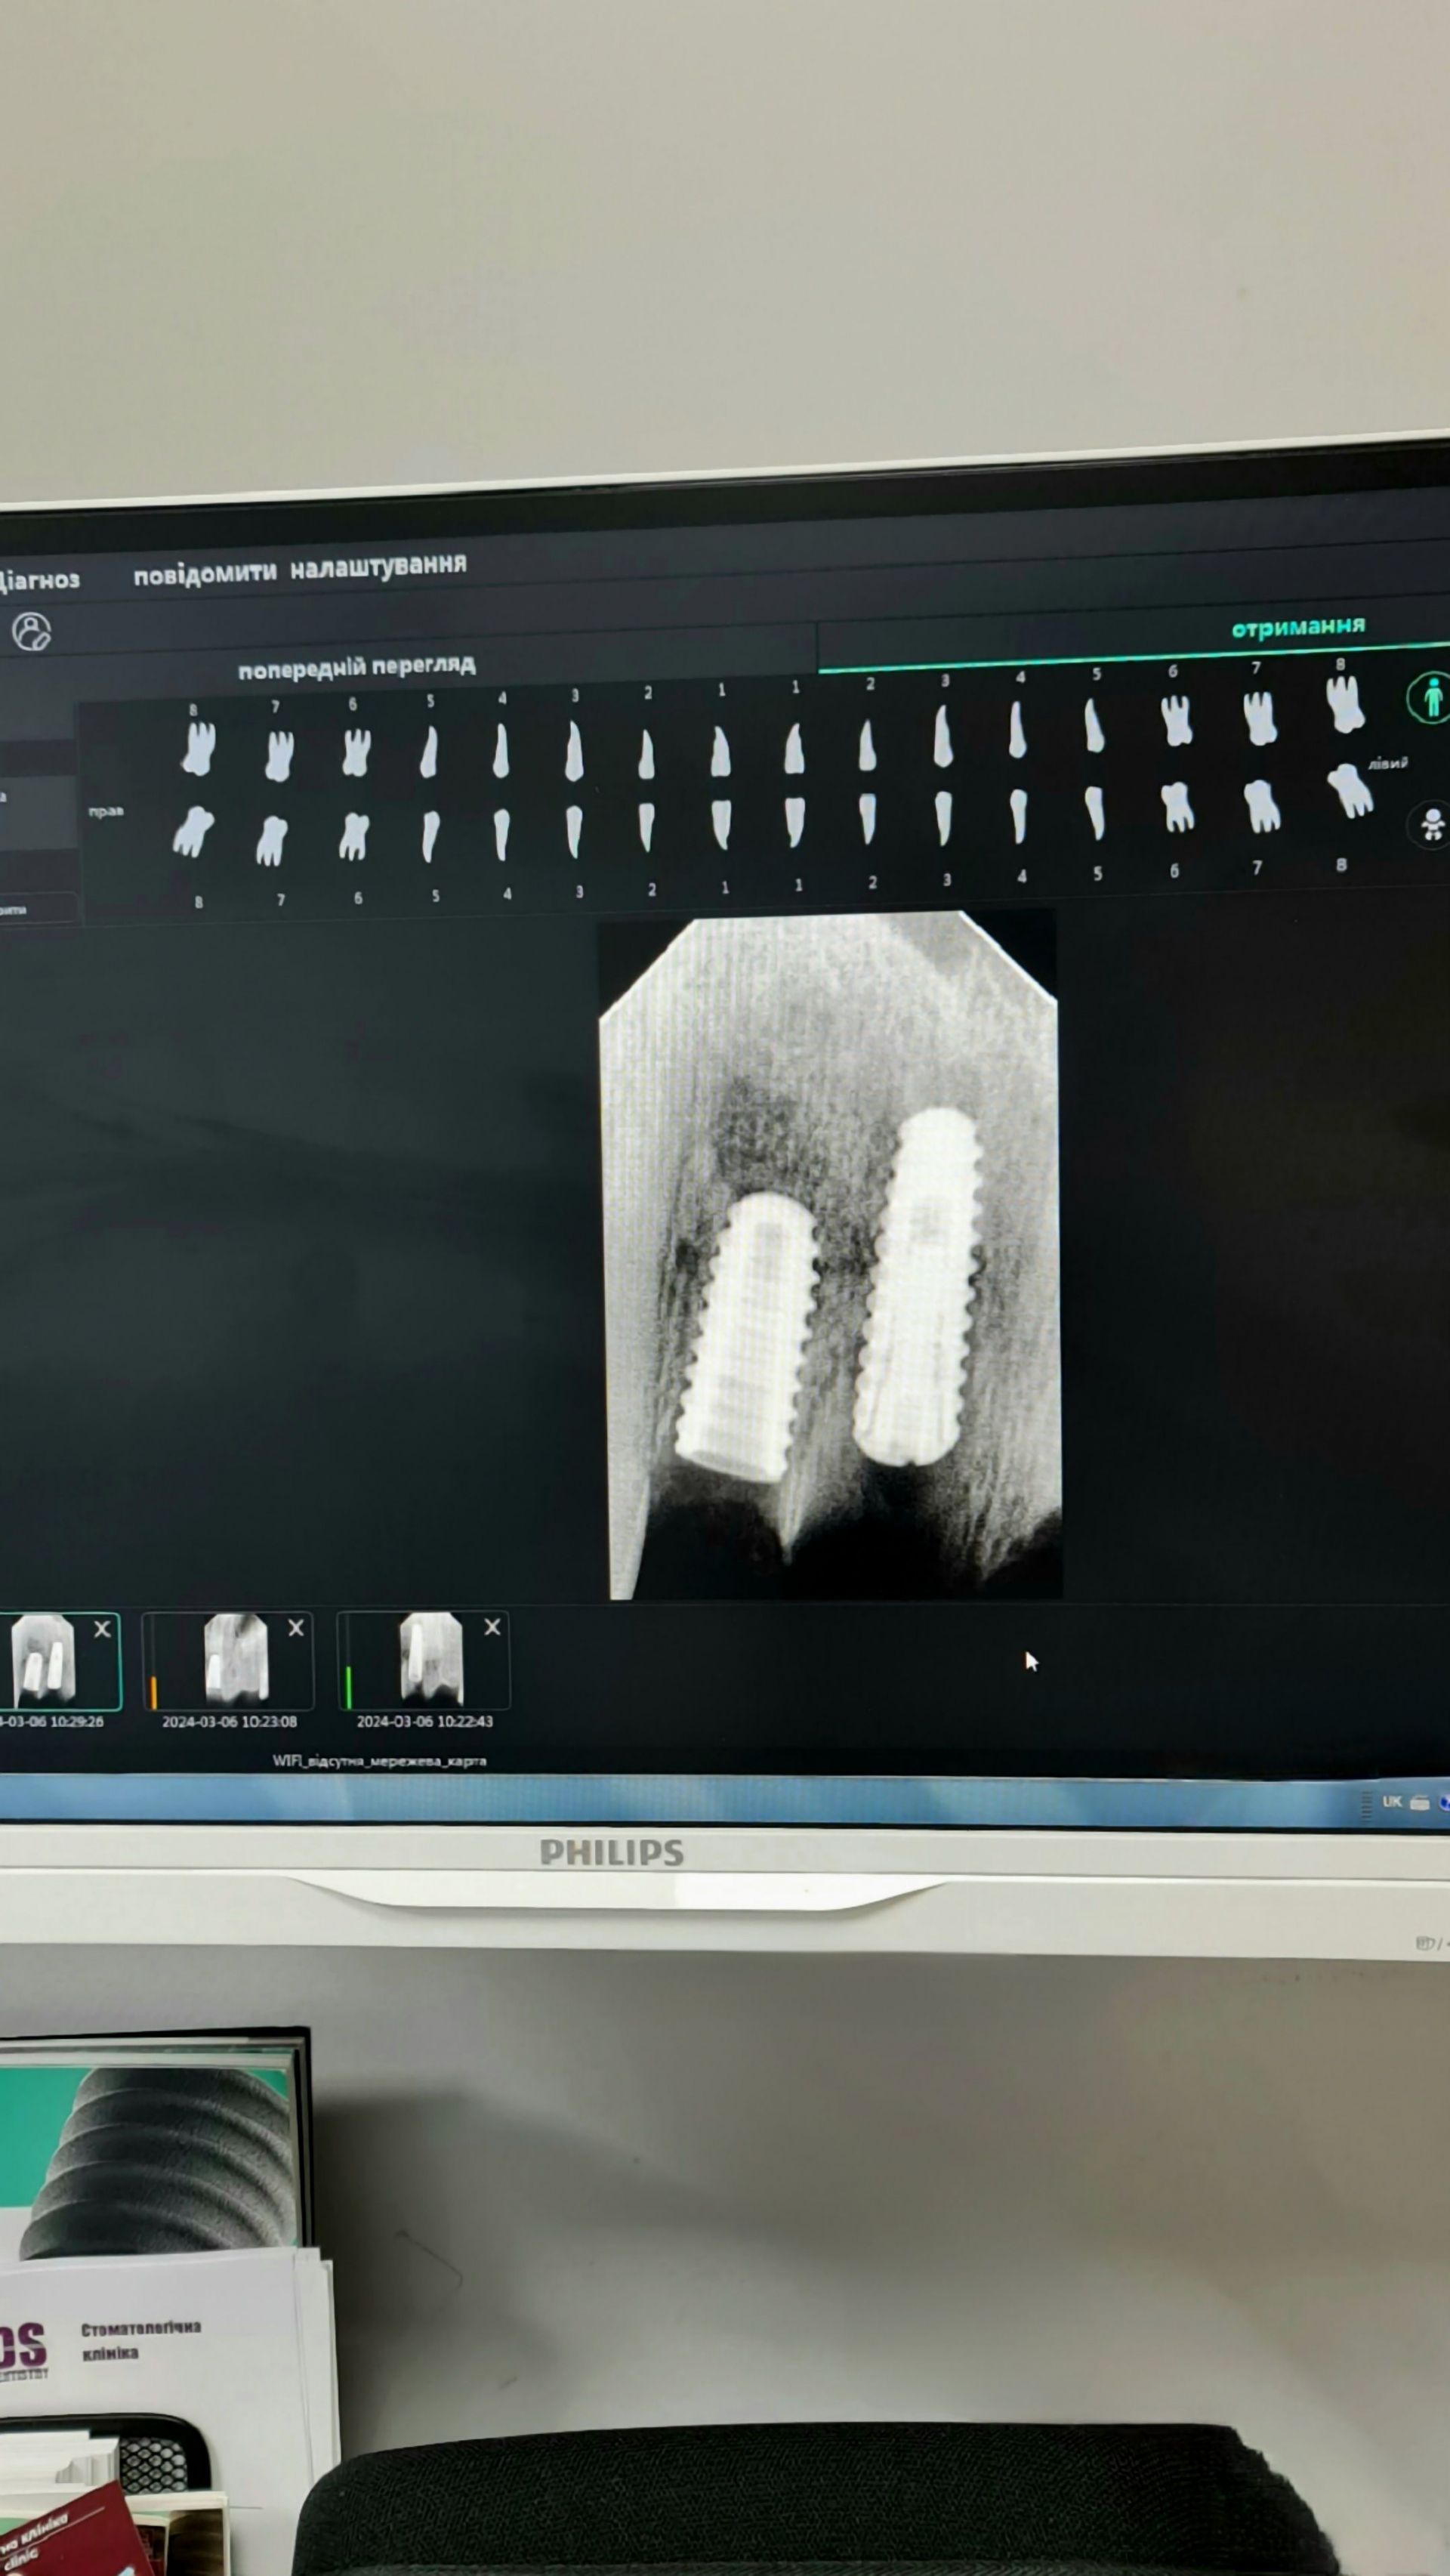

По імплантації

Імплантація - сучасний метод відновлення втрачених зубів.

Імплантат – це аналог кореня зуба, який зроблений зі сплаву металів, де у відсотковому співвідношенні переважає титан. Оскільки матеріали біосумісні з кістковими тканинами, то вони легко приживаються.

Різні виробники додають свої «фірмові» особливості кожного імплантату (наприклад, різні насічки або хімічний спосіб обробки поверхні для кращої первинної стабілізації і подальшого приживлення)